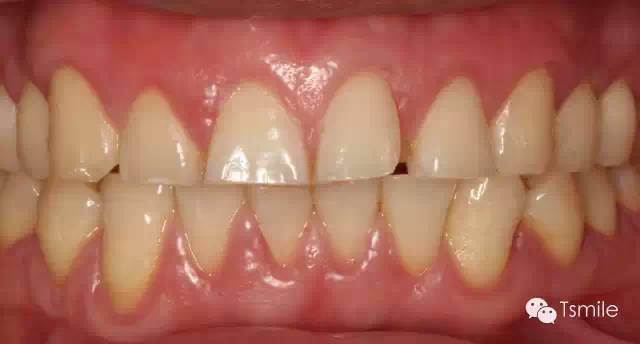

圖2: 長(zhǎng)期飲用碳酸飲料導(dǎo)致的酸蝕癥

磨耗發(fā)生的部位(location)物理性的磨耗由于是上下頜牙列相對(duì)的牙齒之間的機(jī)械摩擦而導(dǎo)致,因此物理性的磨耗主要發(fā)生在牙齒的咬合面。而酸蝕癥導(dǎo)致的牙列重度磨耗不一定在牙齒的咬合面,可以發(fā)生于牙齒的唇頰面或者舌顎面。

物理性的磨耗形成的磨耗面邊緣尖銳、表面光滑閃亮。而酸蝕癥導(dǎo)致的磨耗面邊緣圓鈍,多呈杯狀凹陷。